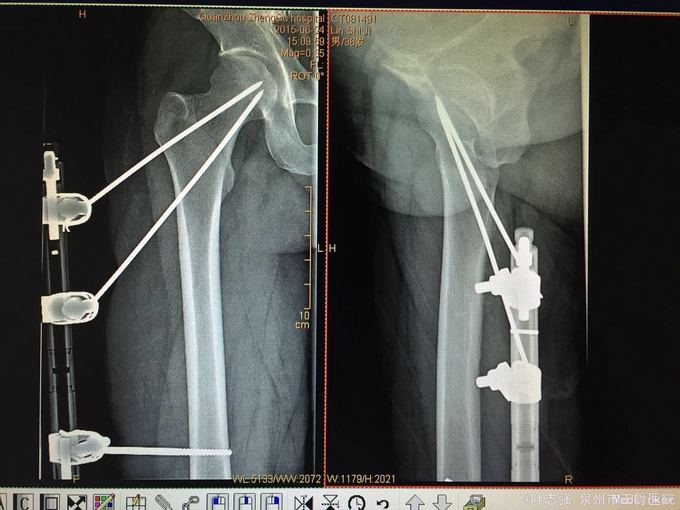

稳定型粗隆间骨折外支架固定

骨折 股骨粗隆间骨折

摔伤致右髋部疼痛、活动受限12小时。 2米高坠落,右髋部着地,当即出现右髋疼痛活动受限,自行卧床休息无明显缓解后医院就诊。 既往甲亢病史,长期口服甲硫咪唑片,自诉控制良好。

右髋部稍肿胀,皮肤张力尚可,右髋部活动受限,右下肢纵向叩击痛阳性,肢端感觉血运活动正常。

右股骨粗隆间骨折 (Evans I型) 甲亢 予行闭合复位外固定支架固定术

术后40天复查骨折线模糊,予取出外支架。